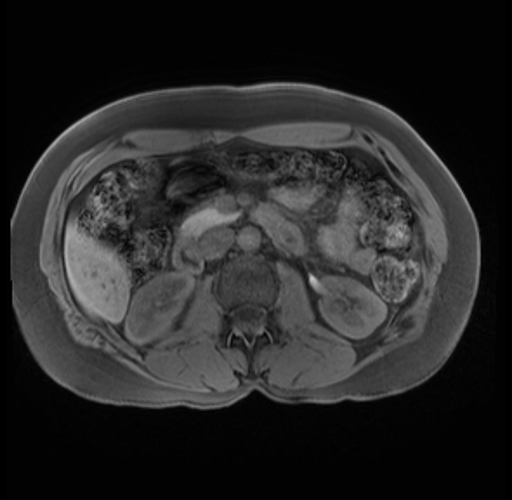

Imaging Analysis

Look through the patient's CT scan to identify any areas of concern for the necessary procedure.

Based on your CT findings, which issue(s) are present and would give reason for "planned slowing down moment(s)" in this case?

Considering a standard distal pancreatectomy procedure, what step(s) of the operation would you do differently in this case?